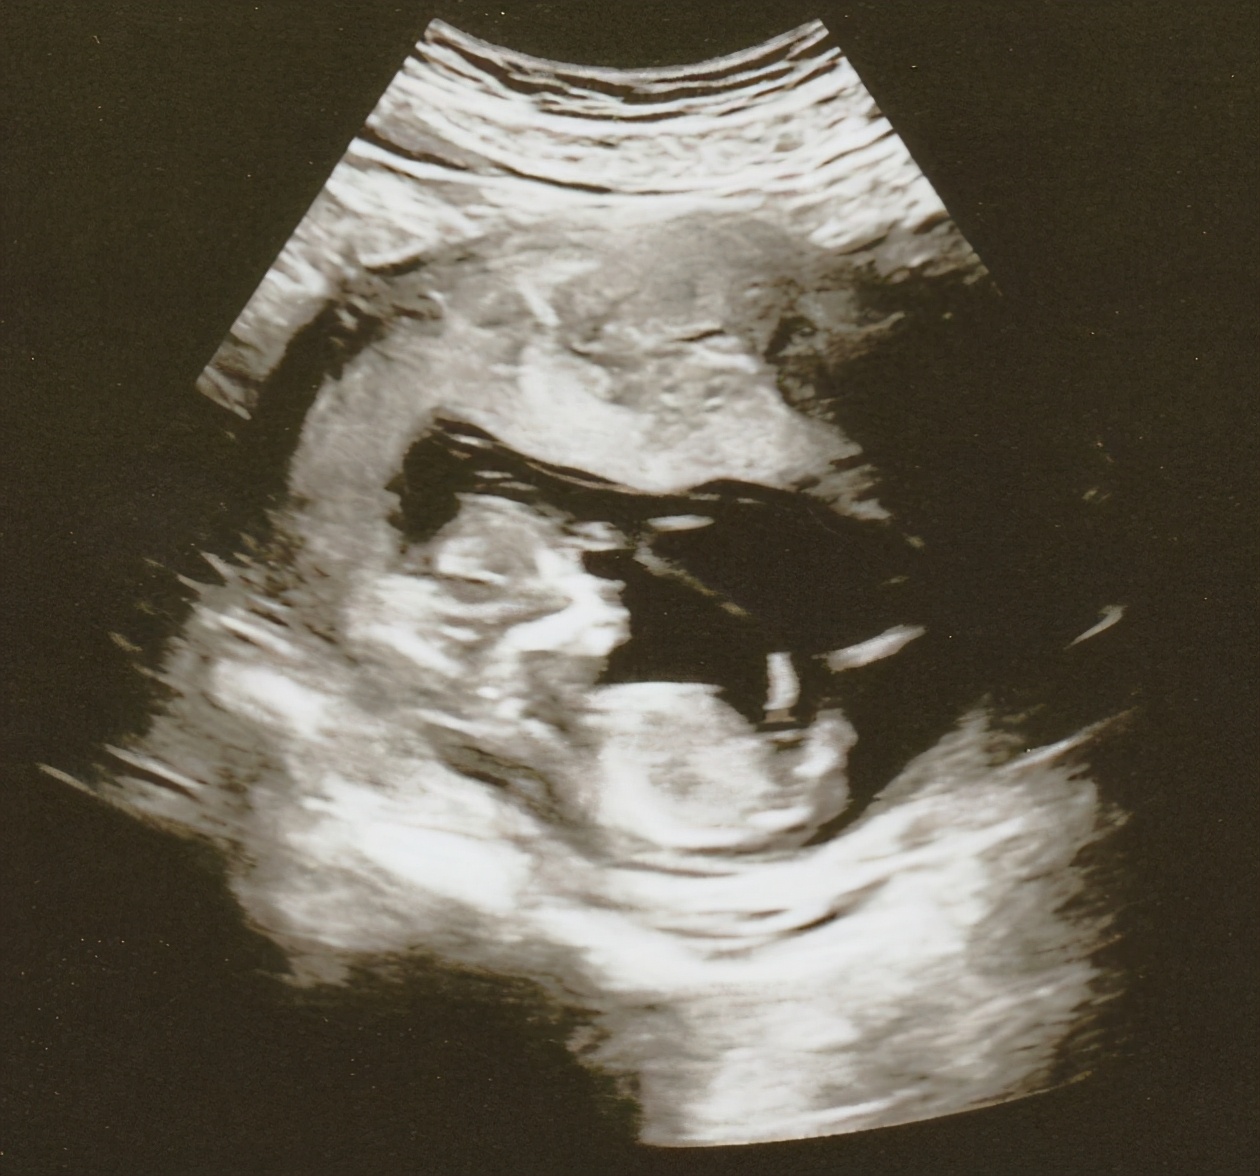

据港媒报道,昨(15)日,庄韵澄在个人社交网贴出一张BB超声波的图片,她开心报喜,正式宣布自己已经怀有4个月身孕,预产期大约在明年中,庄韵澄夫妇即将迎来一位「牛年BB」,原来婚前跟老公早已经成功造人,恭喜呀!

庄韵澄又坦言孕肚目前未算明显,所以她亦十分期待腹中胎儿渐渐长大:「可能BB要再大个点,肚子变大后才有变化,现在可能太小了,我还未能感觉到BB的存在,但我去看医生时就觉得好奇妙,因为照超声波时,我听到BB心跳的卜卜声,原来多了一个生命在自己的身体里。」